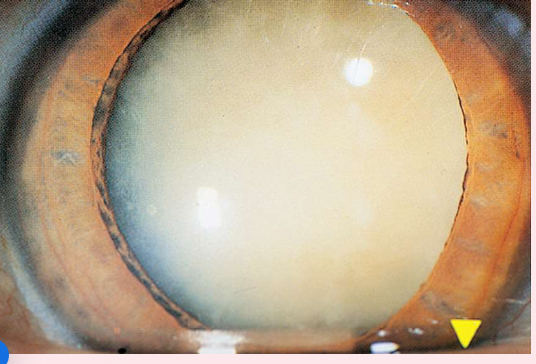

Nuclear cataracts

appear gray when seen with a flashlight; they appear as a black spot against the red reflex

Peripheral cataracts

look like gray spokes that point inward when seen with a flashlight; they look like black spokes that point inward against the red reflex when seen through an ophthalmoscope.